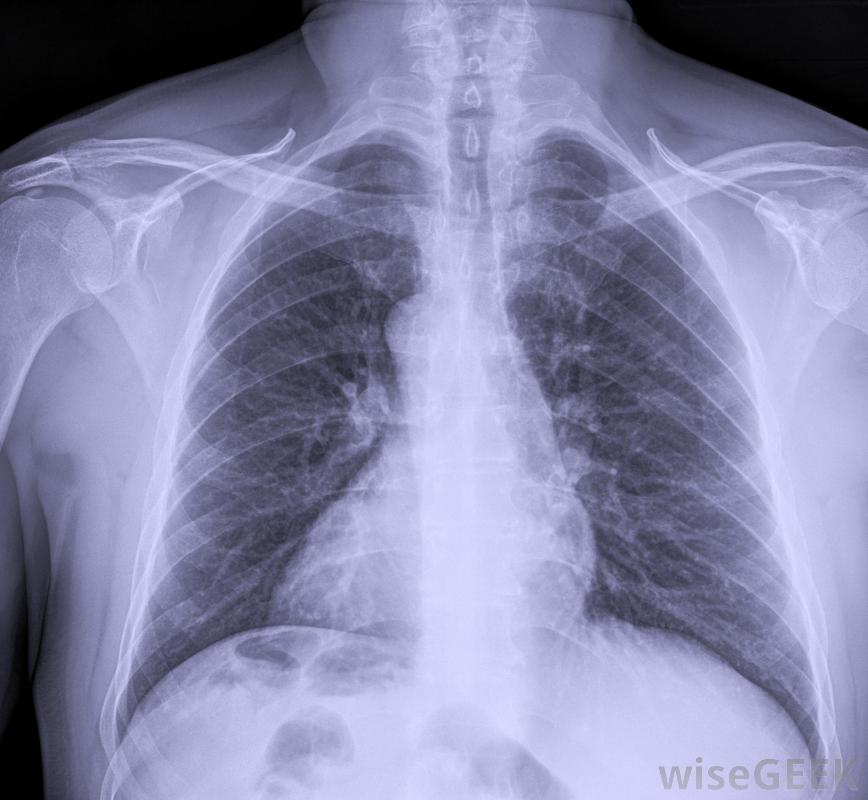

將進行胸部X光檢查,以確保PICC管線正確放置在使用前,

這些類型的靜脈輸液管可以由受過專門訓練的護士、放射科醫生或醫師助理插入。此操作通常在無菌條件下在床邊進行。在放置PICC線后,超聲波用于顯示上臂的大靜脈放置,在使用該線之前,應進行胸部x光檢查以確認放置位置是否正確。